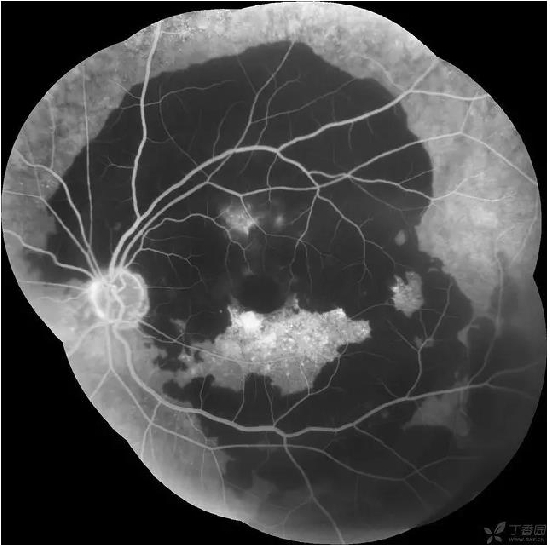

患者,女,74岁。左眼视物模糊3个月。高血压病史。。查体:VOD 0.6 VOS HM 右眼黄斑玻璃膜疣,左眼大片网膜下出血,造影晚期可见荧光渗漏。还是考虑老黄。当时动员她打针,拒绝。半年后复查,变成瘢痕了,照相是小瞳孔下拍的,所以不全。